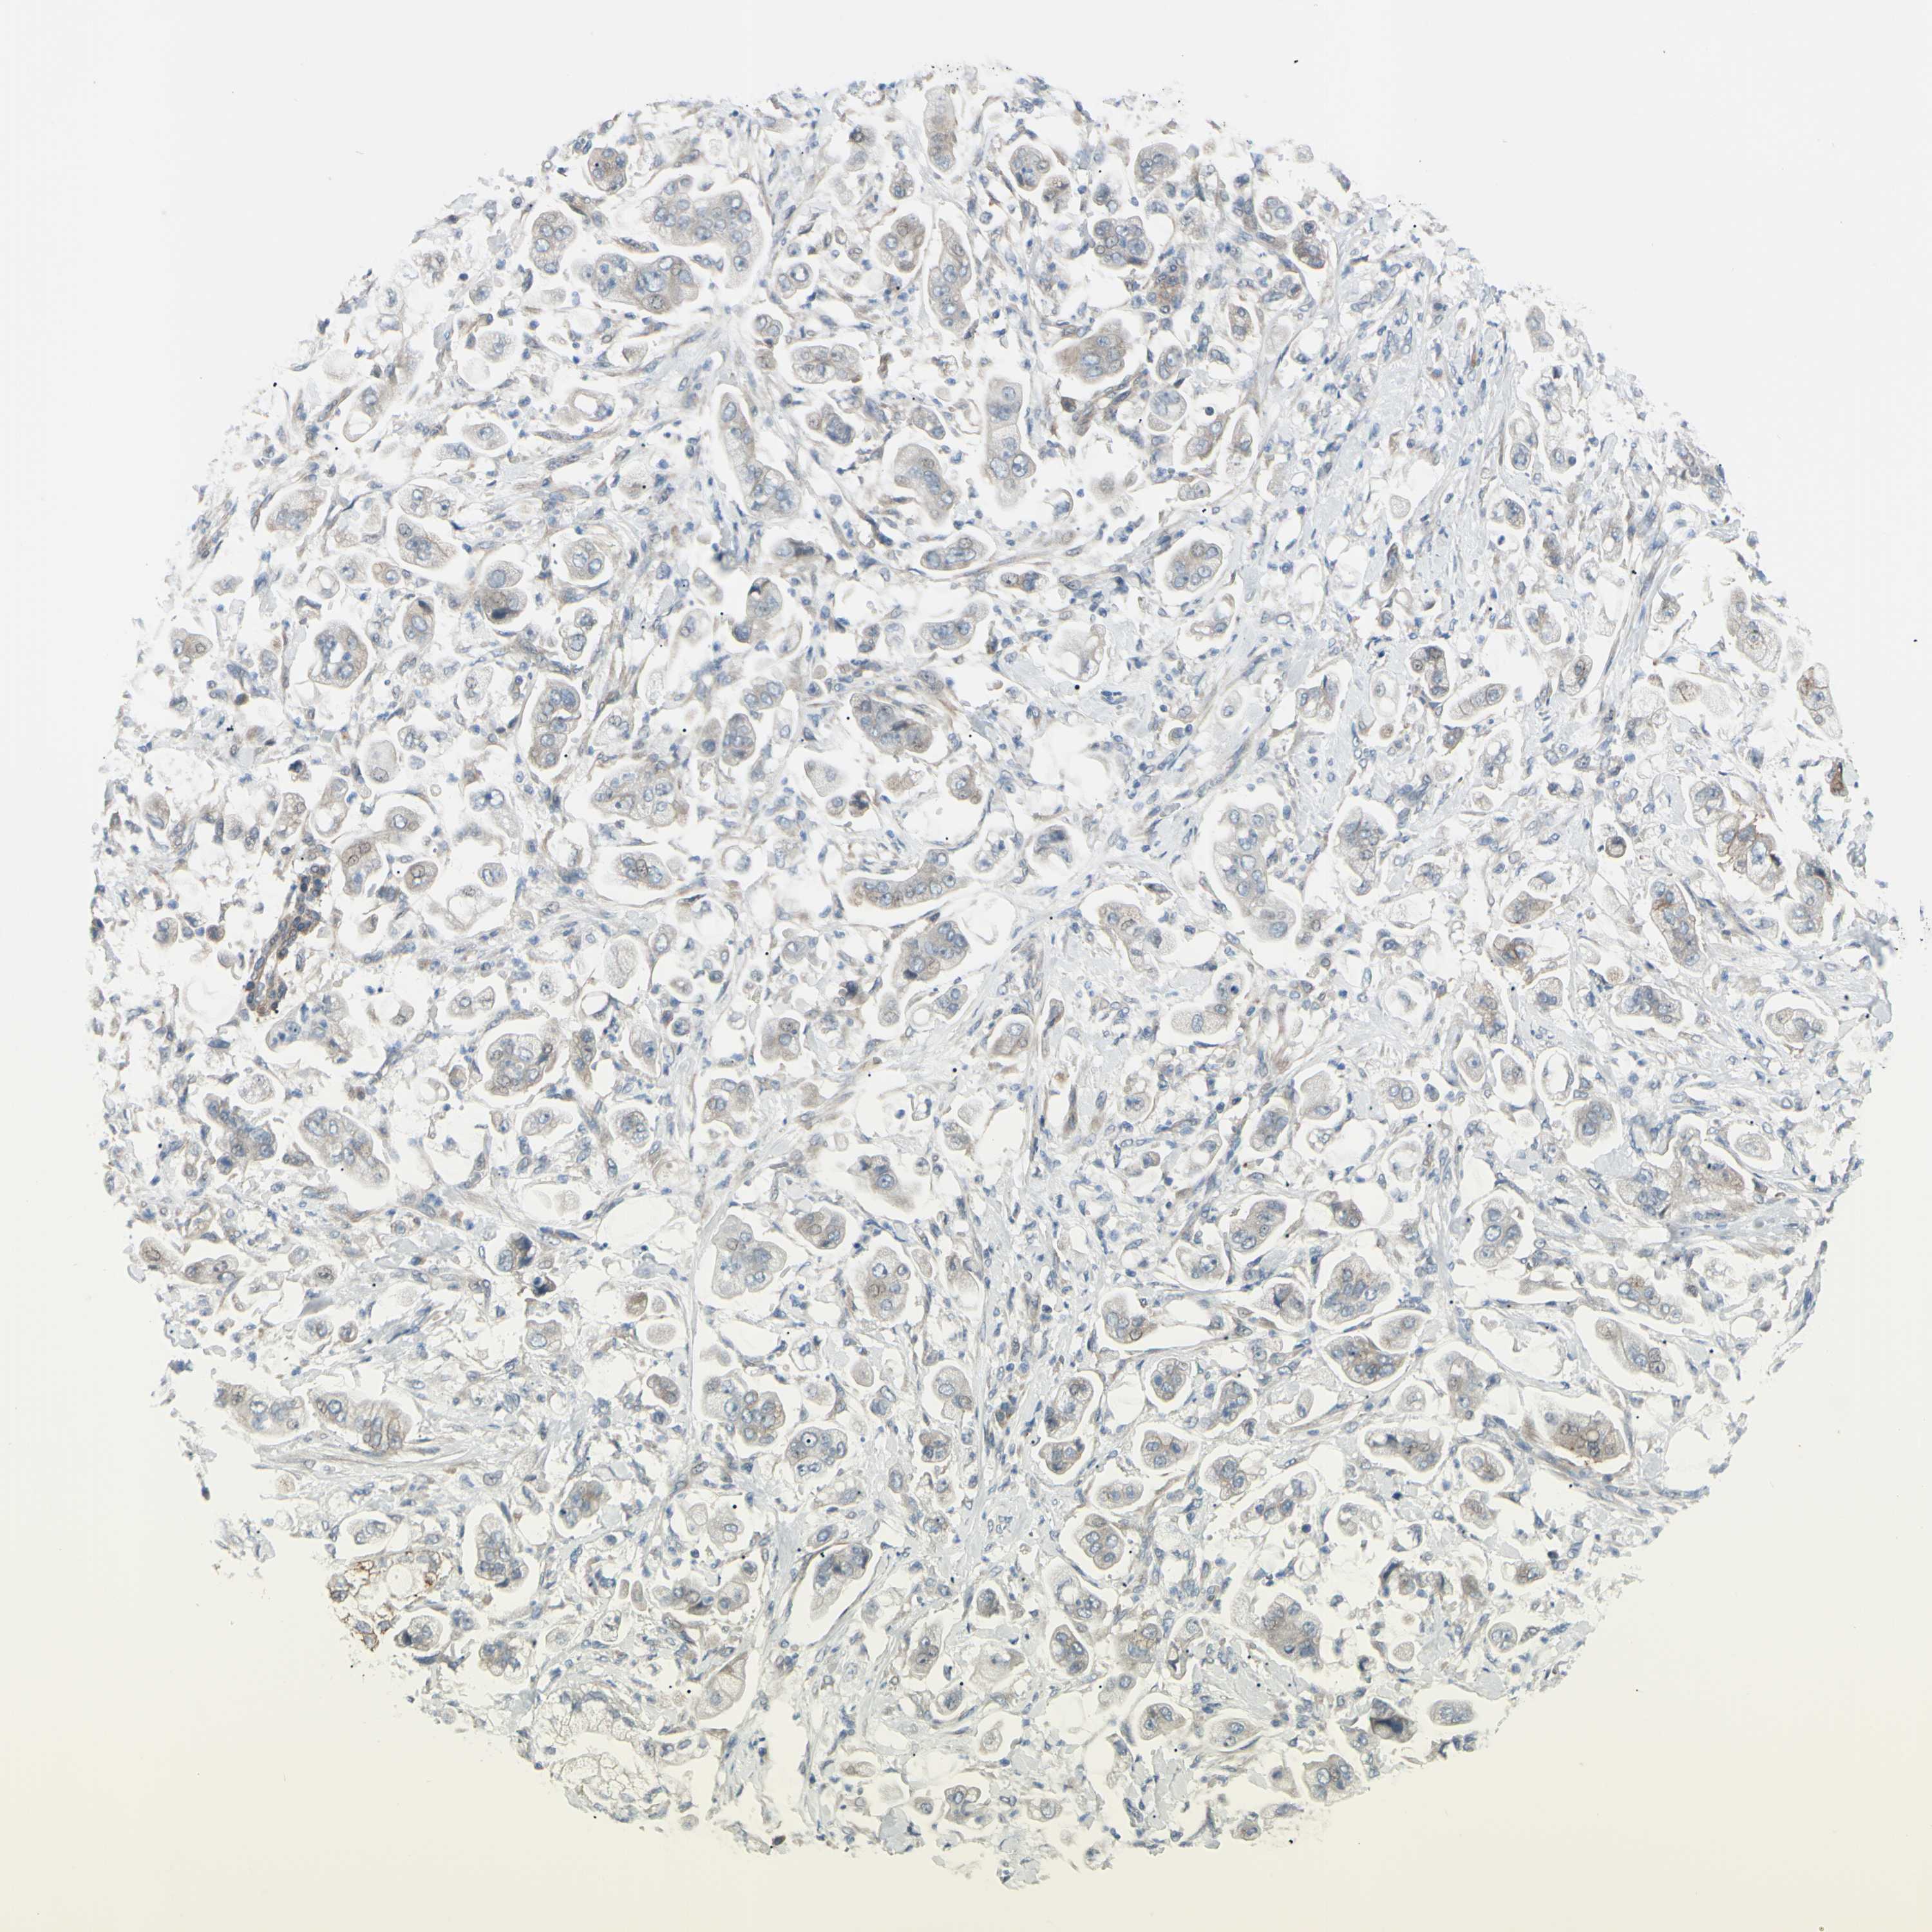

STOMACH CANCER - Protein expressioni

A mouse-over function shows sample information and annotation data. Click on an image to view it in a full screen mode. Samples can be filtered based on level of antibody staining by selecting one or several of the following categories: high, medium, low and not detected. The assay and annotation is described here.

Note that samples used for immunohistochemistry by the Human Protein Atlas do not correspond to samples in the TCGA dataset.

Antibody stainingi

Antibody staining in the annotated cell types in the current human tissue is reported as not detected, low, medium, or high, based on conventional immunohistochemistry profiling in selected tissues. This score is based on the combination of the staining intensity and fraction of stained cells.

Each image is clickable and will lead to virtual microscopy that enables deeper exploration of all samples and also displays staining intensity scores, fraction scores and subcellular localization as well as patient and tissue information for each sample.

Antibody HPA010537

Staining

High

Medium

Low

Not detected

Intensity

Strong

Moderate

Weak

Negative

Quantity

>75%

75%-25%

<25%

None

Location

Nuclear

Cytoplasmic/membranous

Cytoplasmic/membranous,nuclear

Adenocarcinoma, NOS

Adenocarcinoma, High grade